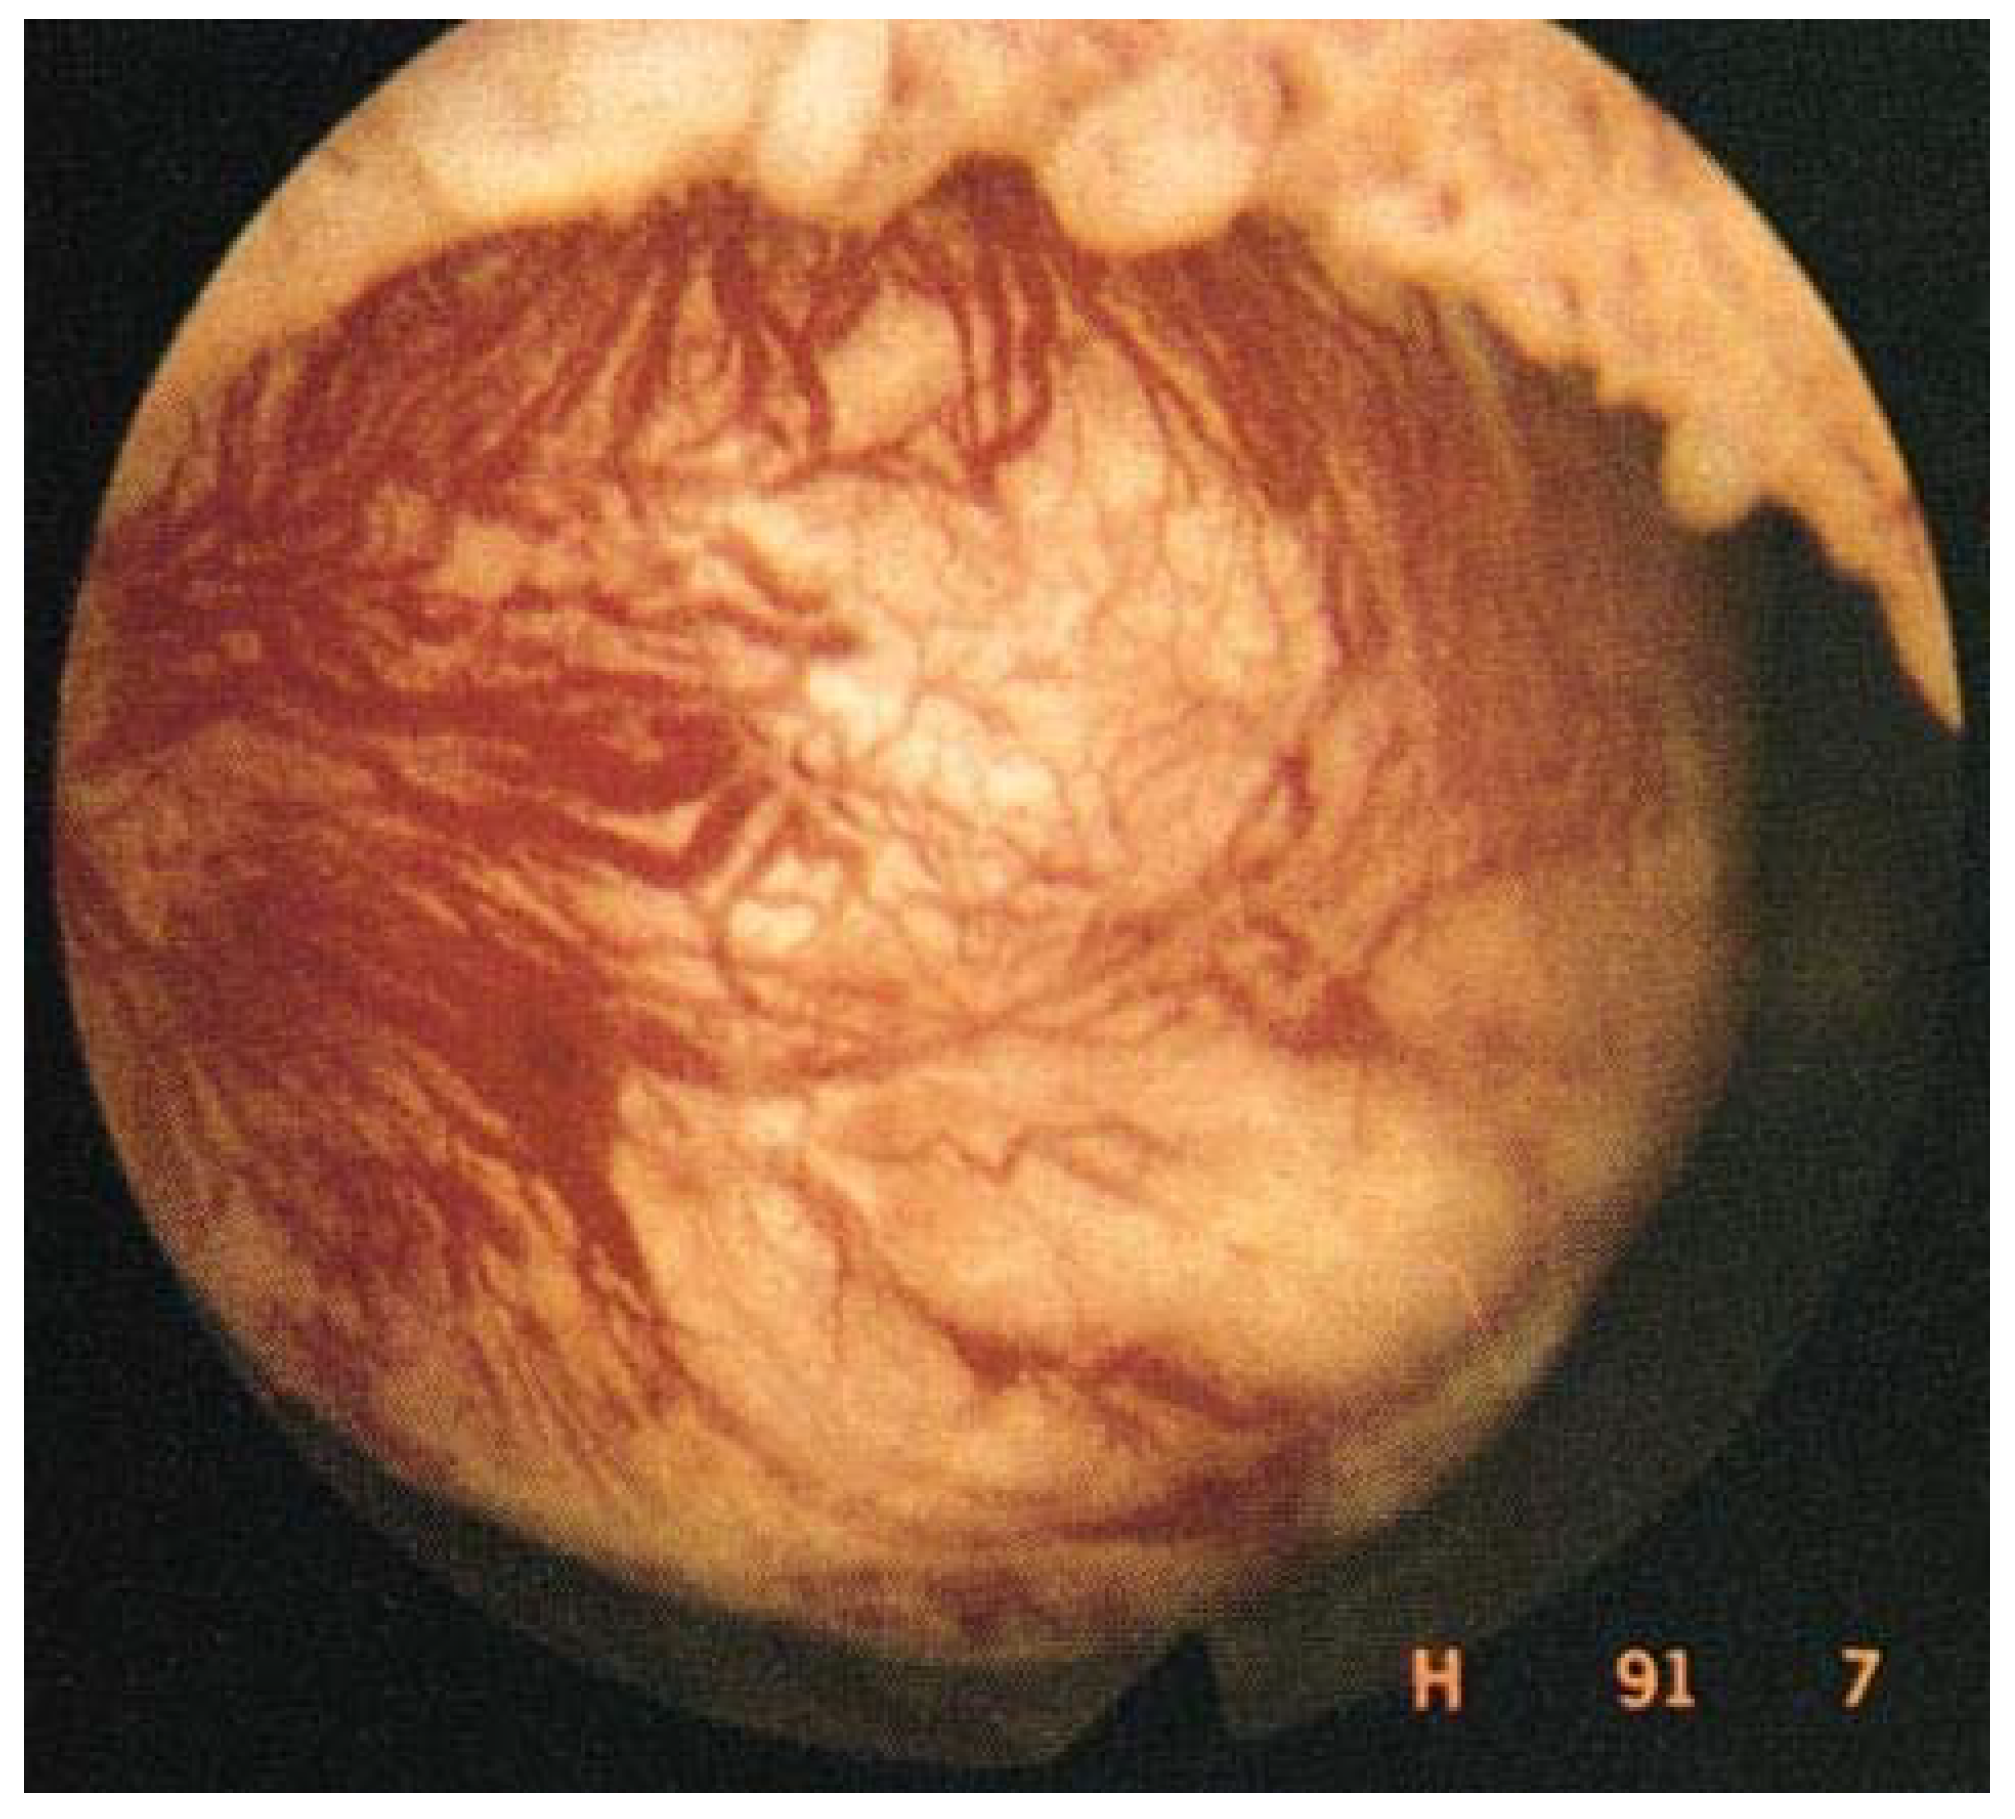

2.2. Presence of Dilated Blood Vessels on the Myoma Surface